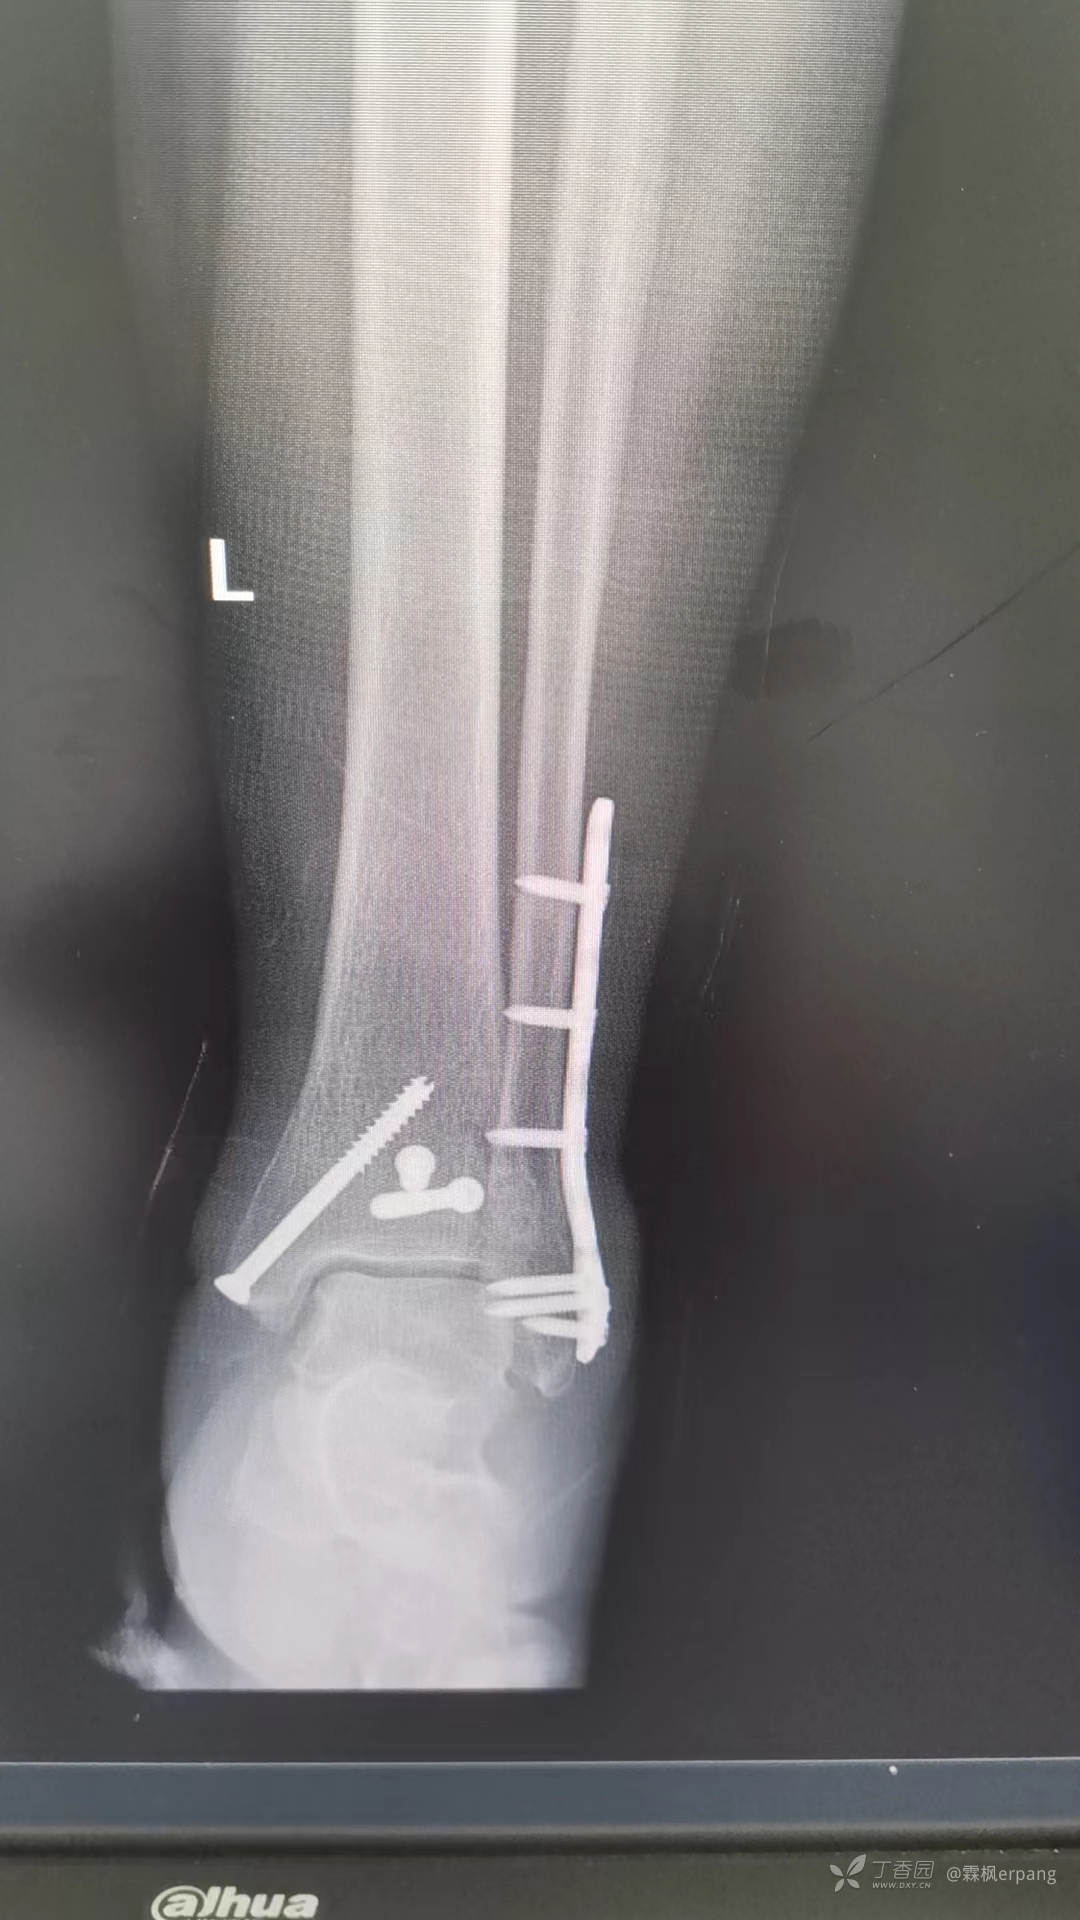

手术计划:后外侧切口做外踝和后踝,内侧闭合空心钉内固定。

术中钢板近端略偏前,无碍大局,未做调整。

术后片